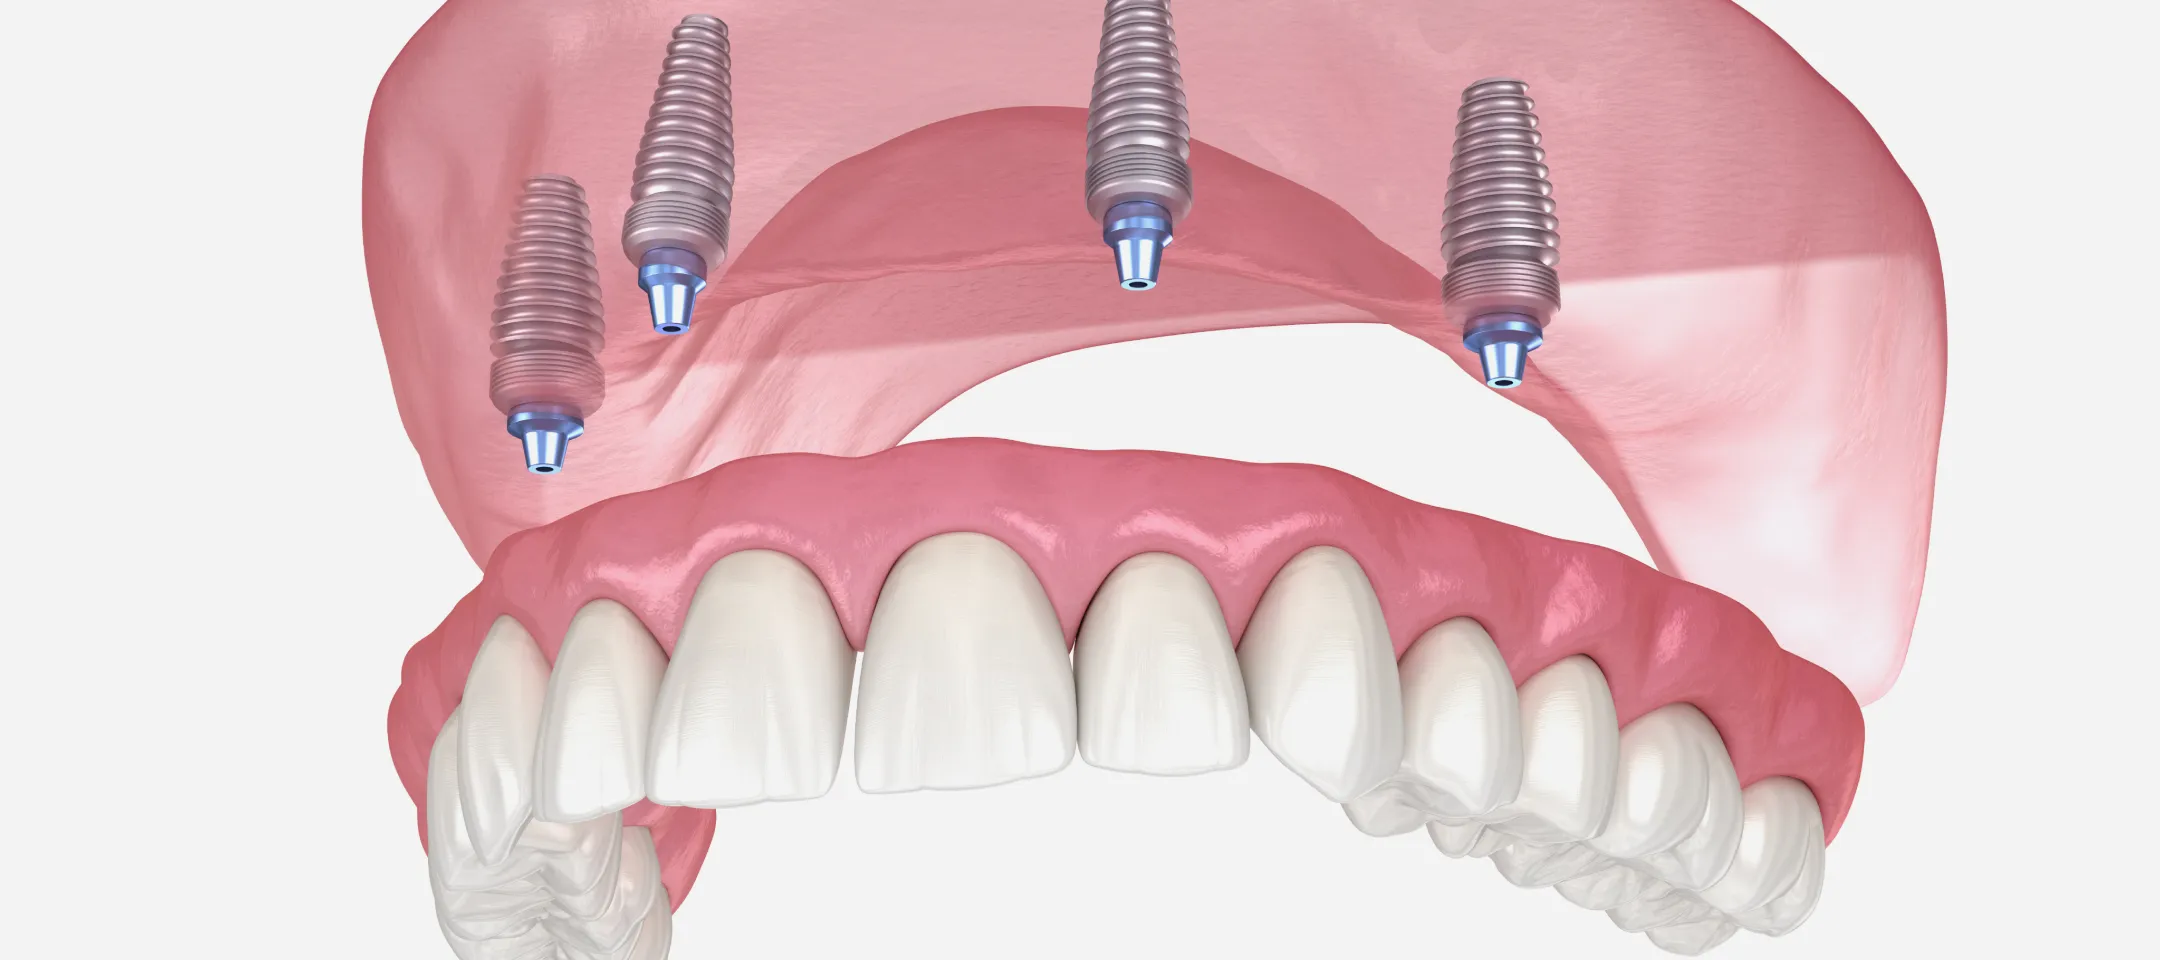

総入れ歯を使用されている方の中には、「しっかり噛めない」「外れるのが怖い」と不便を感じている方が多くいらっしゃいます。オールオンフォーは、片顎に4本前後のインプラントを埋め込み、その上に取り外し不要の固定式の人工歯を装着する治療法です。違和感を抑えつつ安定感のある噛み心地を得やすいのが特徴です。

上顎:ピンクポーセレンを用いたフルジルコニアインプラントブリッジ(All-on-4)

下顎:ピンクポーセレンを用いたフルジルコニアインプラントブリッジ(All-on-4)治療期間 1年 費用 上顎:330万 税抜

オールオンフォー/シックスでは、奥歯のインプラントを斜めに埋入する独自の方法を採用します。これにより骨のある部分を有効に使い、片顎4~6本という少ない本数で全体を支えることが可能になります。

従来の治療では歯を失った本数に近い数のインプラントを必要とすることが多く、骨移植や大がかりな骨造成を伴うケースも少なくありませんでした。これに対しオールオンフォー/シックスは、骨の状態を最大限活かしながら安定した支持を得られるのが大きな特徴です。

さらに、インプラントは骨と結合する性質があるため、強固な土台として機能します。その上に装着する人工歯は色や形を調整でき、自然で快適な仕上がりを目指せます。